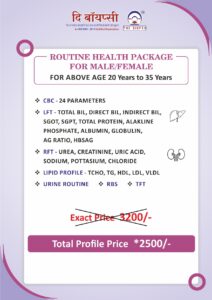

Our Health Packages

We Provide All Types of Diagnostics Services and its Health Pacakages also.